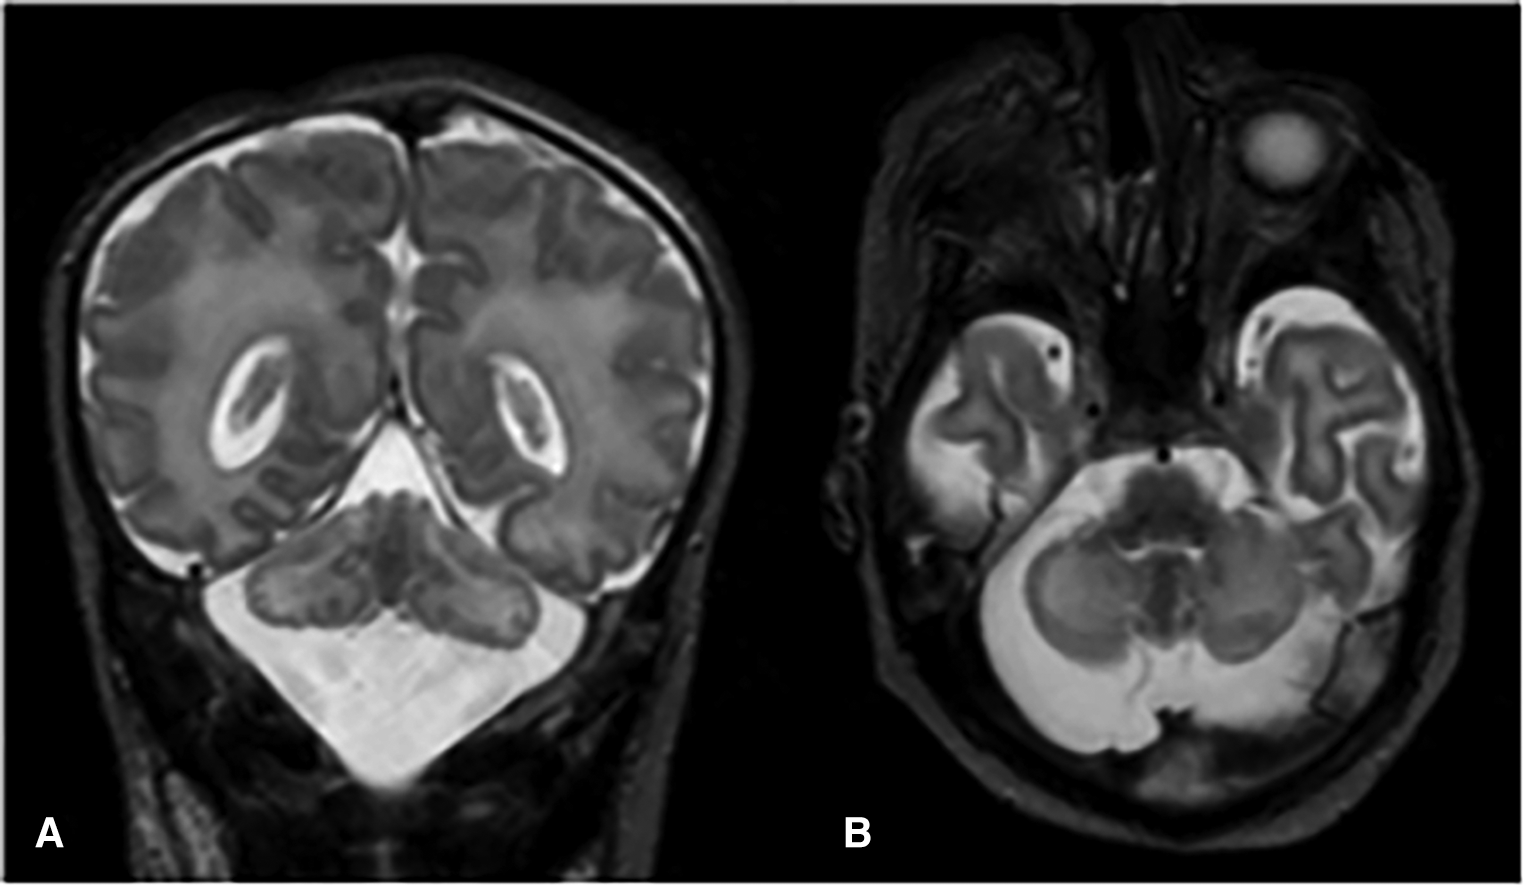

Absence of neurological improvement prompted extended metabolic and endocrine evaluations: the levels of serum amino acids, sialotransferrin, TSH, free T4, cortisol, ammonia, and 17 OH progesterone were found to be within normal range. Urine amino acid analysis detected mild elevation (11 mmol/mol creatinine) in excretion of 3-methylglutaconic acid, implying possible mitochondrial dysfunction (14). Brain MRI on day 6 showed cerebellar hypoplasia with symmetric involvement of the vermis and hemispheres, without dysplasia (Figure 1) and a potential ischemic thalamic lesion (Figure 2).

Figure 1

Coronal (A) and axial (B) T2-weighted images show global cerebellar hypoplasia with symmetric involvement of both hemispheres and vermis, along with a very large cisterna magna. There was no obvious abnormality of the brainstem. The cerebellar folia and fourth ventricle were not dilated, indicating there was no volume loss. The cerebellar foliation pattern was normal and there were no heterotopic nodules of gray matter, indicating there was no dysplasia.